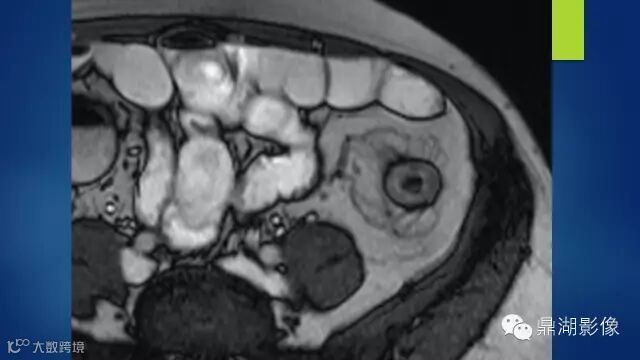

what's the meaning of fat halo sign?

粘膜下水肿或脂肪沉积,可致肠壁内呈低密度层(halo征),其最初用来描述溃疡性结肠炎,是良性肠道病变的结果,无特异性,也可存在于放射性肠炎,移植-受体疾病和慢性缺血性肠炎以及单性的肥胖症患者。

Fat halo aslo can be seen in normal terminal ileum.